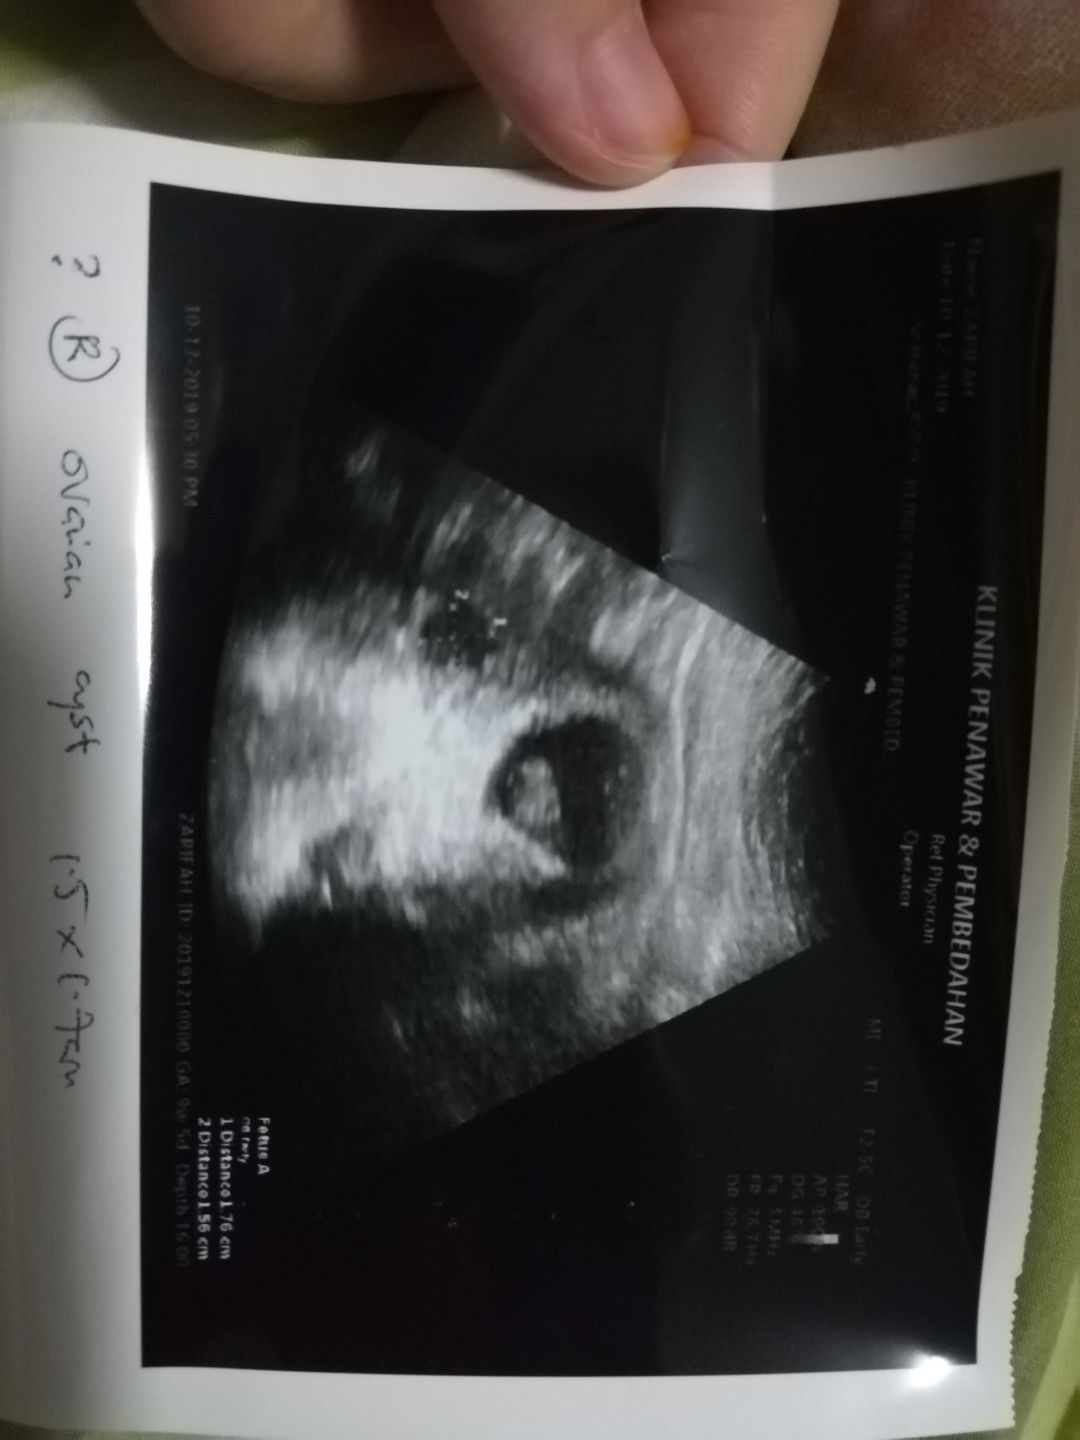

cyst

Bru scan.. Klo ikut pengiraan last period.. 9w5d Tp td scan saiz fetus 8w6d.. Lewat seminggu.. Tp Alhamdulillah heartbeat positif.. Tp srlain fetus.. Dokte nmpk jugak ade cyst.. Saiz 1.5cmx1.7cm.. Ade pernah ade pengalaman.. Hamil n mempunyai cyst.. Adekah mengganggu kehamilan..